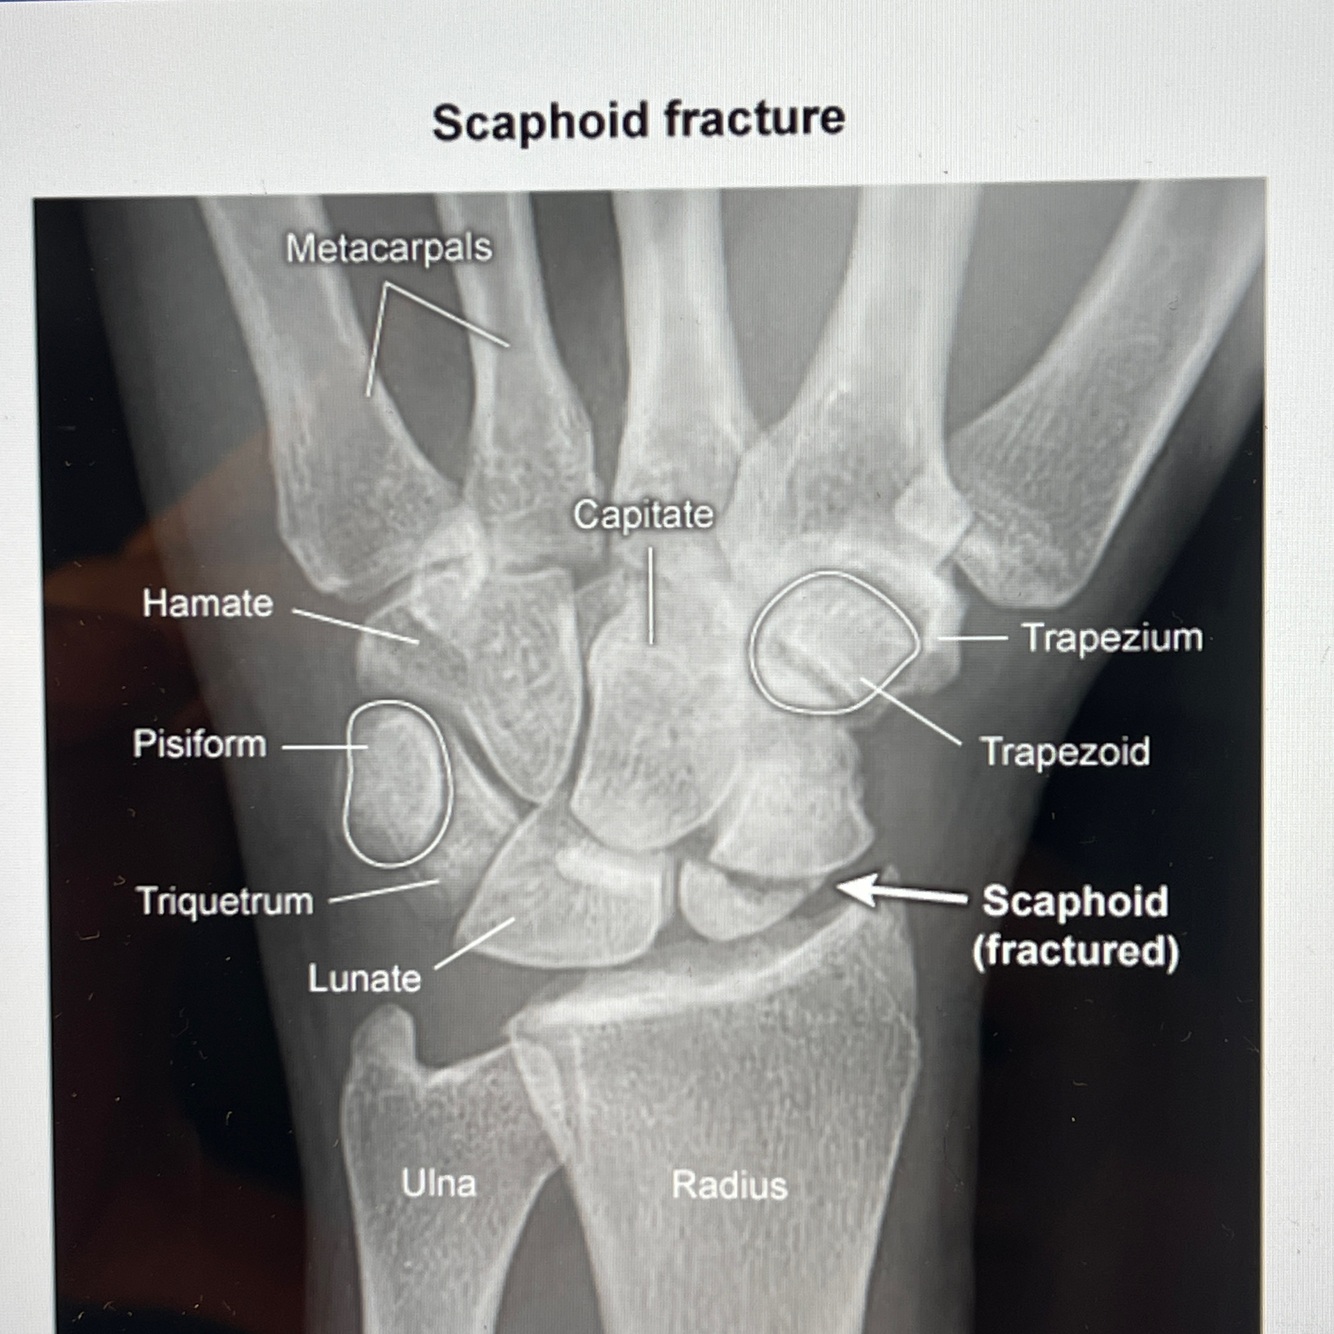

A

How well did you know this?